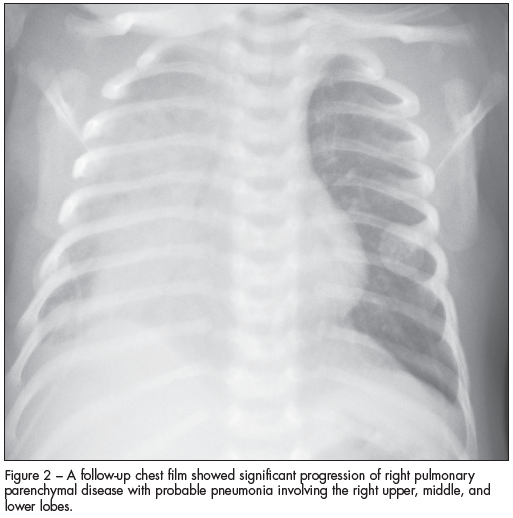

The patient had mild upper respiratory tract symptoms for 2 days.